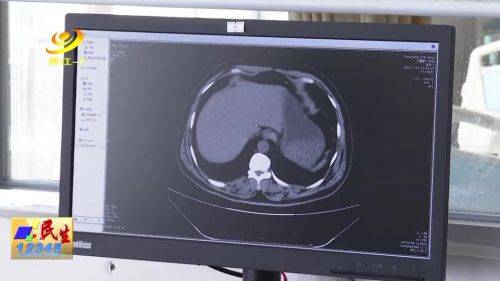

上午 , 采访人员从市中医医院消化内科医生了解到 , 肝炎是由细菌、病毒、酒精、药物、自身免疫系统等多种致病因素引起的肝脏炎症统称 , 目前 , 已明确的肝炎有甲型、乙型、丙型、丁型、戊型五种类型 , 五种类型临床表现比较相似 , 早期会出现食欲减退、倦怠、乏力 , 厌油 , 最后出现肝功能异常 。

市中医医院消化内科主治医生 张思荣:对于乙型、丙型、丁型这三类倾向于慢性感染 , 它们的传播途径主要是血液、体液和胃肠道 。 慢性肝炎感染者会出现黄疸 , 最后会出现肝硬化、肝癌情况 , 往往这类病人会发展成中晚期症状 , 出现并发症 , 患者后期不加以防范的话通常会死于并发症 。

【丁型|医生提醒:预防肝炎,接种疫苗注意饮食是关键】据世界卫生组织发布数据显示 , 目前全球大约有3.25亿人感染慢性肝炎 , 在我国 , 慢性肝炎的发病率及死亡率较高 。 其中 , 大部分肝癌病例是由病毒性肝炎所致 。 据介绍 , 目前 , 甲肝、乙肝和戊肝均有疫苗 , 而丙肝尚无疫苗 。